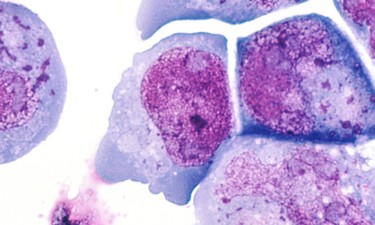

Células de cáncer. | Wikipedia Estudio en 'Nature' Nuestro sistema inmune tiene traidores entre sus filas 2 comentarios Investigadores holandeses han descubierto que células del sistema inmunitario pueden propagar también células cancerosas.

Células de cáncer. | Wikipedia PI(3)K/AKT/mTOR, la molécula culpable ¿Por qué los fármacos no terminan de vencer al cáncer? Quo 4 Algunas células cancerosas desarrollan resistencia a los medicamentos, por lo que el cáncer se sigue extendiendo tras la eficacia inicial.